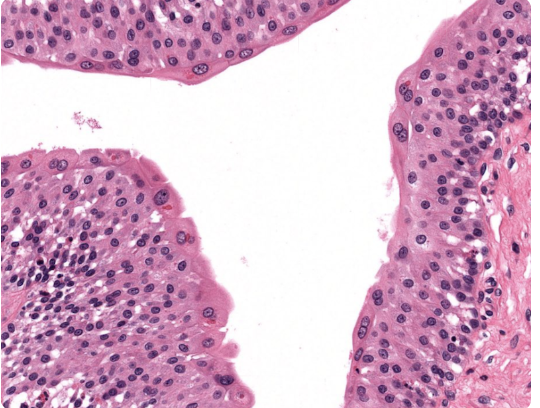

Epithelial Tissues Matching Game

Test your knowledge about epithelial tissues with this fun matching pairs game!